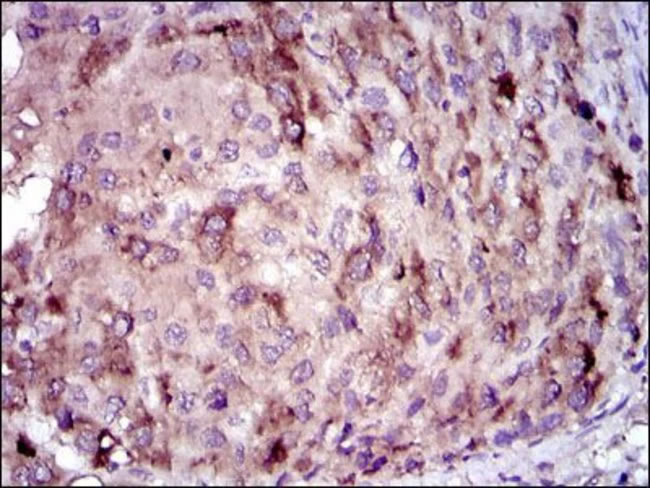

海角社区联免疫吸附测定(ELISA);免疫组织化学(IHC);蛋白质印迹法(免疫印迹试验WB); 免疫荧光(固定细胞)(IF/ICC); 免疫沉淀(IP); 细胞ELISA(cELISA); 免疫测定(IA); 免疫细胞化学(ICC)

相关图谱